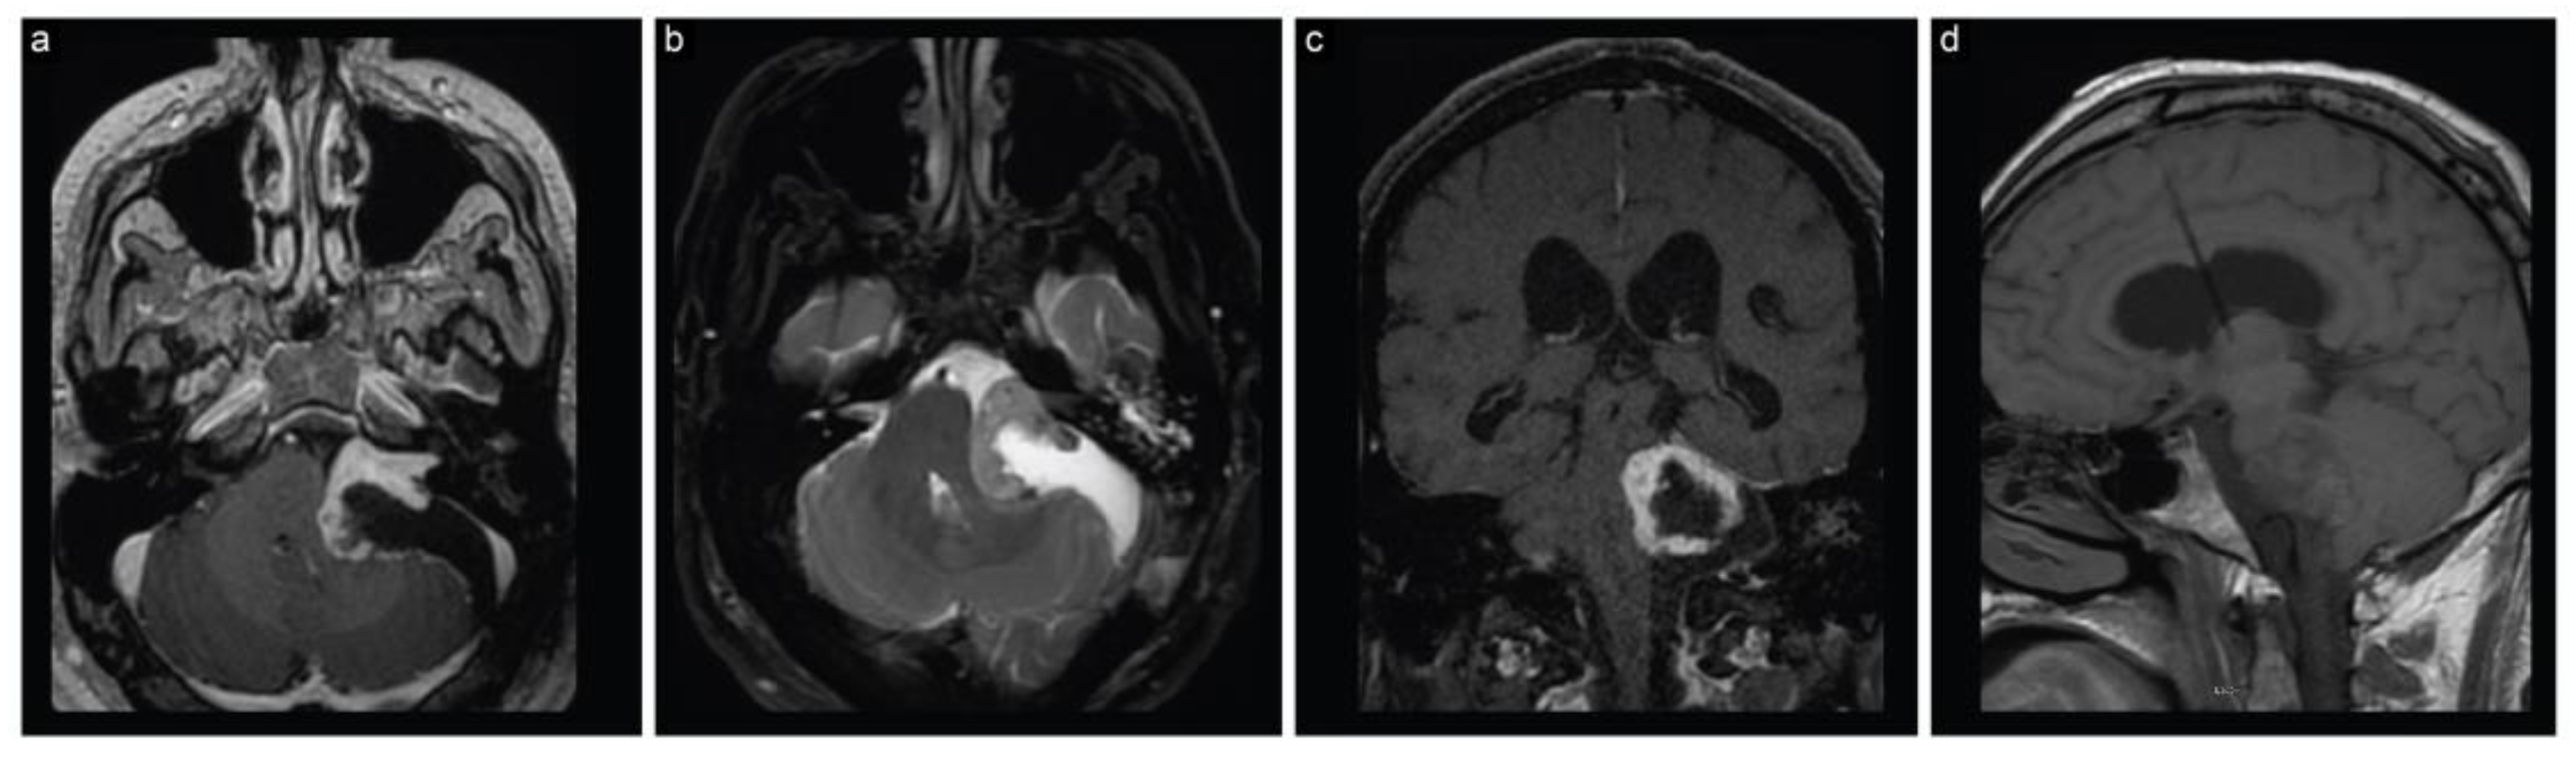

The patient woke up with House–Brackmann grade I facial nerve function. The histopathological diagnosis was confirmed as a WHO grade I schwannoma. An early postoperative MRI revealed partial resection of the tumor and decompression of the brainstem and surrounding structures, along with regressed hydrocephalus (Figure 2).

Figure 2.

Case 1 post-stage 1 neuroimaging findings. (a) Axial T1-weighted postcontrast, (b) axial T2-weighted, (c) coronal T1-weighted postcontrast, and (d) sagittal T1-weighted MRI scans show partial resection with decompression of the brainstem and surrounding structures along with regressed hydrocephalus.